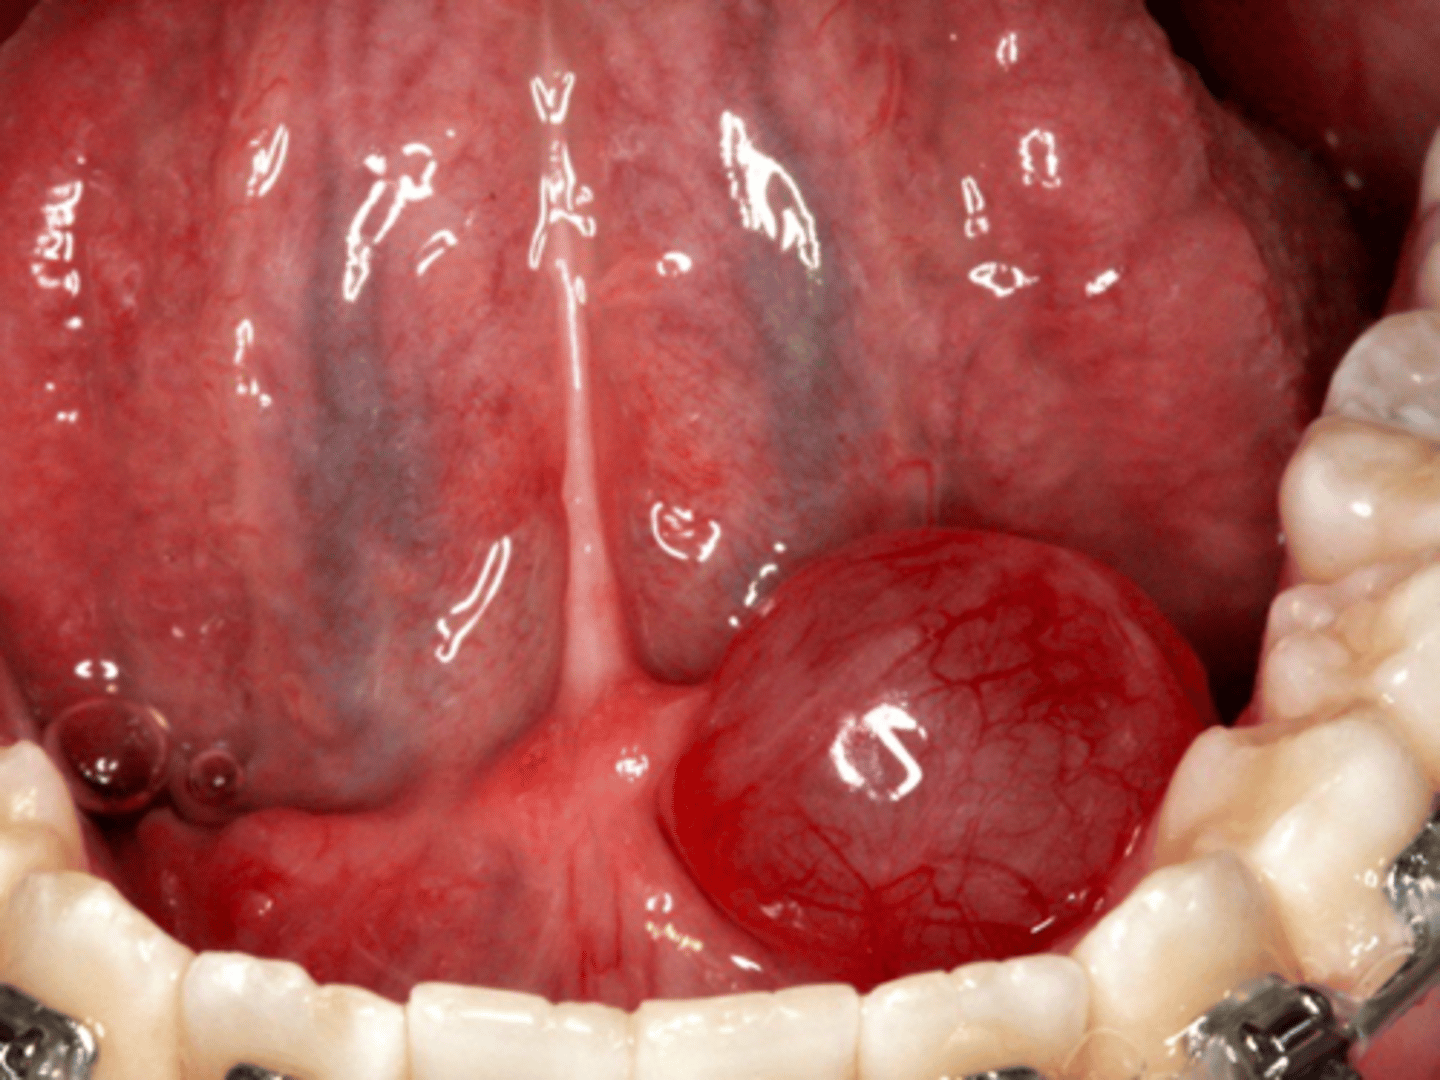

Ranula

A mucocele on floor of mouth is called a ______

sublingual gland

A Ranula is usually associated with what gland?

mylohyoid

A plunging ranula variant dissects through the _______ muscle into neck

patient presents with a dome-shaped fluctuant vesicle that looks bluish in color on the floor of the mouth. What is the diagnosis?

floor of mouth

what is the most common location for a Ranula to present?

ID the pathology:

- Ranula

- Salivary duct cyst

- Dermoid/Epidermoid cyst

Patient presents with a large nodule on the floor of the mouth lateral to the midline. What is in your differential diagnosis (3)?

Excisional biopsy with gland

What is the treatment for a ranula?